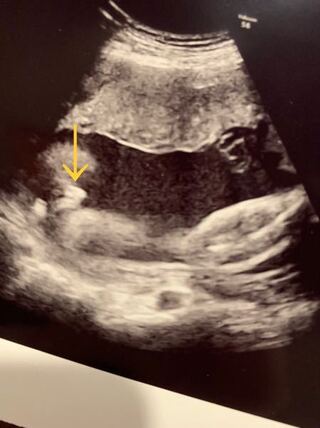

妊娠週 21w0d 性別判明し男の子でした。 友人や職場の人にずっと女の子と言われていたので先生に男の子と言われた時はパパと2人で笑ってしまいました。 可愛い顔も見せてくれて思い出いっぱいのエコー写真になりました。 おなまえ cn ねんれい 25 妊娠 男の子が女の子に間違えられる場合や女の子が男の子に間違えられる可能性もあるといわれています。 エコー検査にはさまざまな種類がある まずエコー検査には、どんなものがあるのでしょうか。主なものとして以下のような種類があります。 2dエコー エコー写真撮影時のエピソード: また顔隠毎回撮影する瞬間に顔を隠してしまいます。 またお股もなかなか開いてくれないので、性別もなかなか分かりません。 きっと、ママパパが女の子かなー?男の子かなー?って毎日話してるのを聞いてるのかな?

なぜ、エコーで「男の子で間違いないよ」と言われていたのに、女の子が生まれてきたのでしょうか? 通常の性別判定では、男の子の象徴がエコーで見えると「男の子だよ」と先生から言われます。 しかし、エコーは細部まで必ずしも正確に見えるものではありません。 出産したら女の子だっエコーでおしりの方をみていると 「ん~、ここが割れ目っぽく見えるから、女の子の可能性の方が高いかな」 きゃーーーーーー 女の子!女の子!!女の子!!! 「男の子だと、ここが矢印状に見えることが多いんだよね。